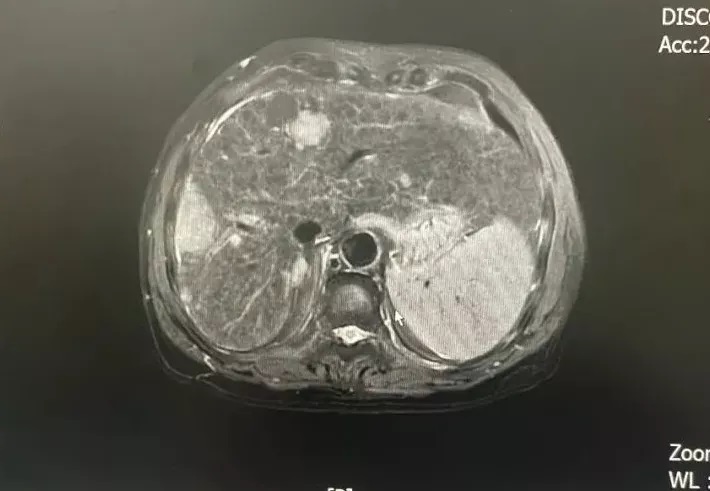

“患癌”噩耗突如其來,他們懵了......

“患癌”噩耗突如其來,他們懵了......和平國(guó)際醫(yī)學(xué)影像中心是致力于疑難病診斷的專業(yè)醫(yī)療機(jī)構(gòu)。作為精準(zhǔn)影像的追尋者,深度健...